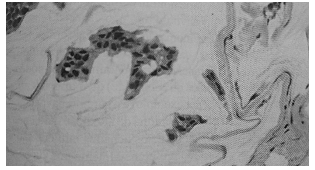

Assinale a alternativa correta que evidencia o diagnóstico para o quadro histológico ilustrado na figura abaixo.

enunciado 540549-1